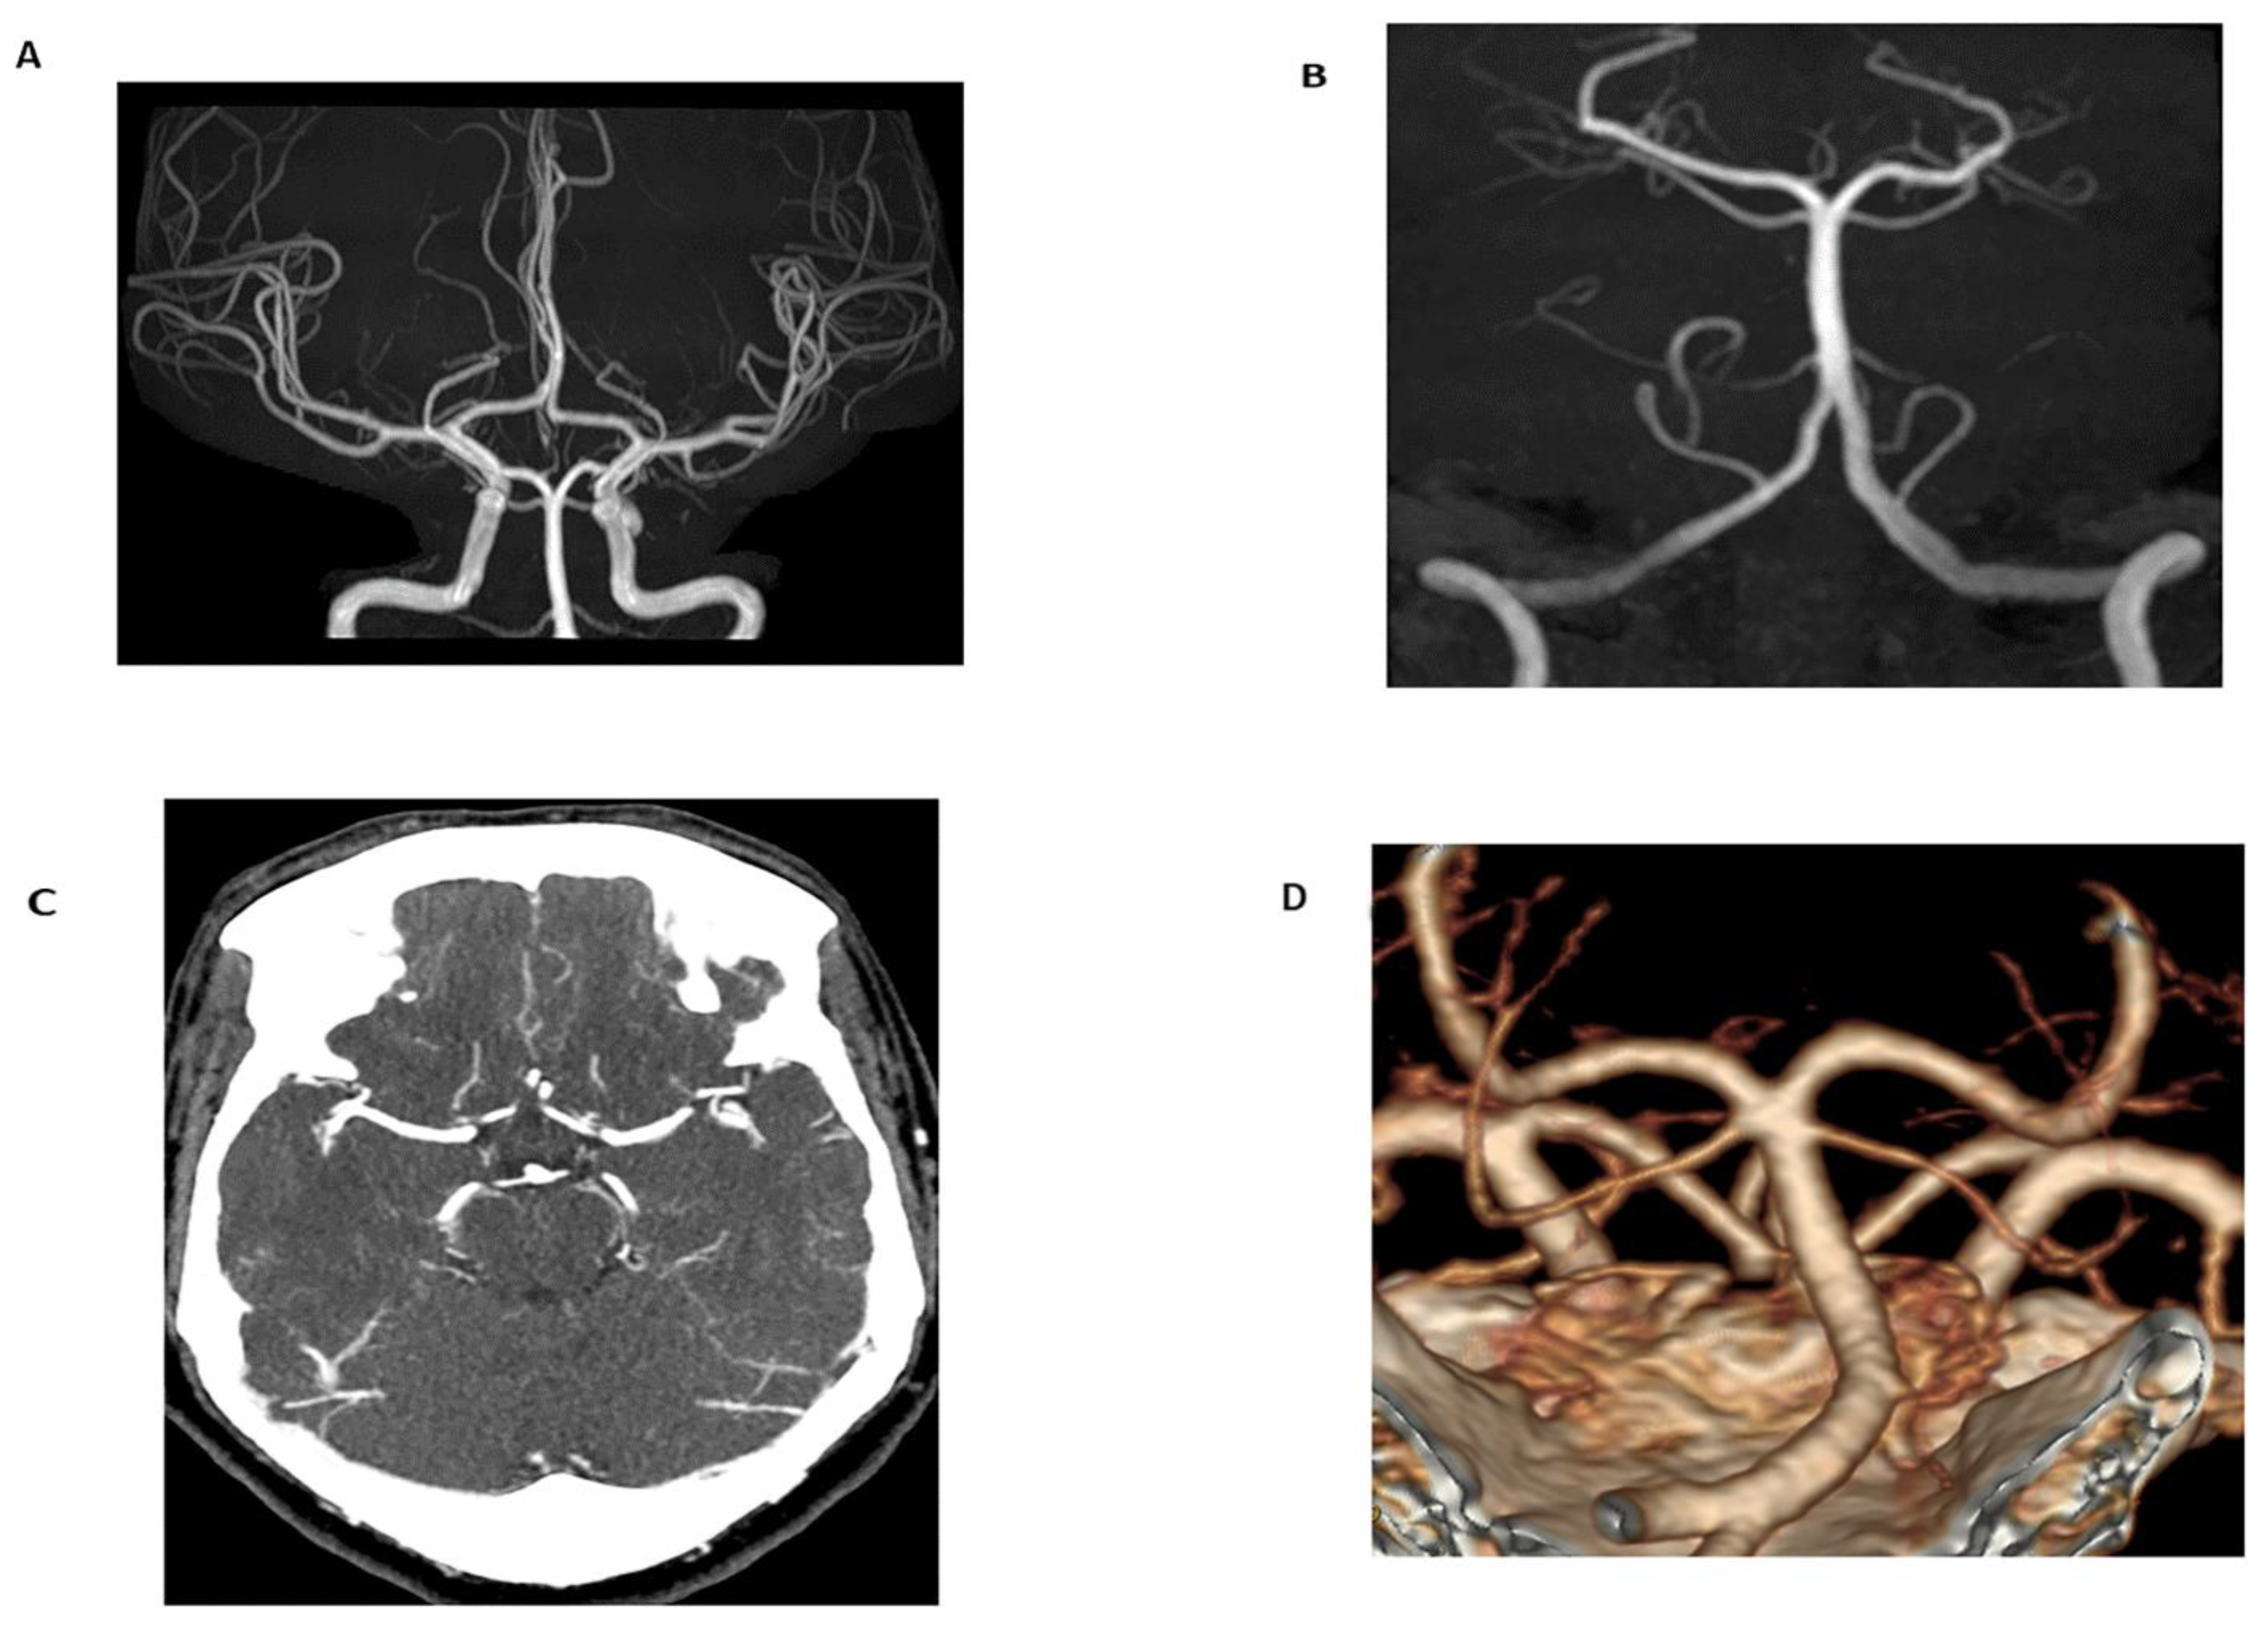

3.2.1. Magnetic Resonance Angiography

3.2.2. Open and Larger Bore MRI